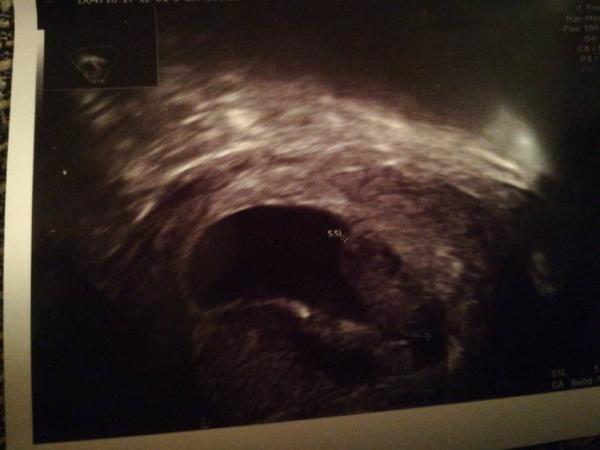

War wieder mal mit starker Blutung und Schmerzen im Krankenhaus.. Was soll ich sagen zuerst war es ne Ader, dann ein abgeganger Zwilling.. Jetzt ein großes hämatom das immer wieder blutet

... Das liegt auch noch so nah am Krümel dem es übrigens gut geht mit 1,7cm und pochendem Herz... Ich bin nervlich am Ende